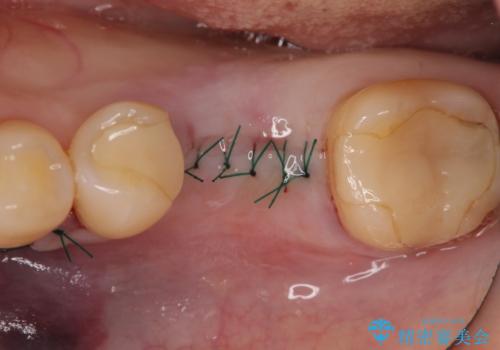

被せ物を外したところ歯が割れており保存不可能だったため抜歯し、インプラントによる欠損補綴を行いました。

- 外科手術のため、術後に痛みや腫れ、違和感を伴います